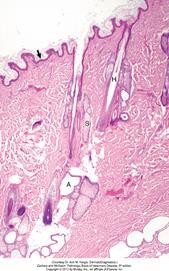

The epidermis (arrow) in haired skin has an undulating surface but lacks rete ridges. The epidermis in haired skin has fewer nucleated cell layers than the epidermis in nonhaired (hairless) skin such as that on the nose and pawpads; thus it is referred to as “thin” skin. Hair follicles (H), apocrine glands (A), and sebaceous glands (S) are present. The haired skin is thickest over the dorsal aspect of the body and on the lateral aspect of the limbs, and it is thinnest on the ventral aspect of the body and the medial aspect of the thighs. H&E stain